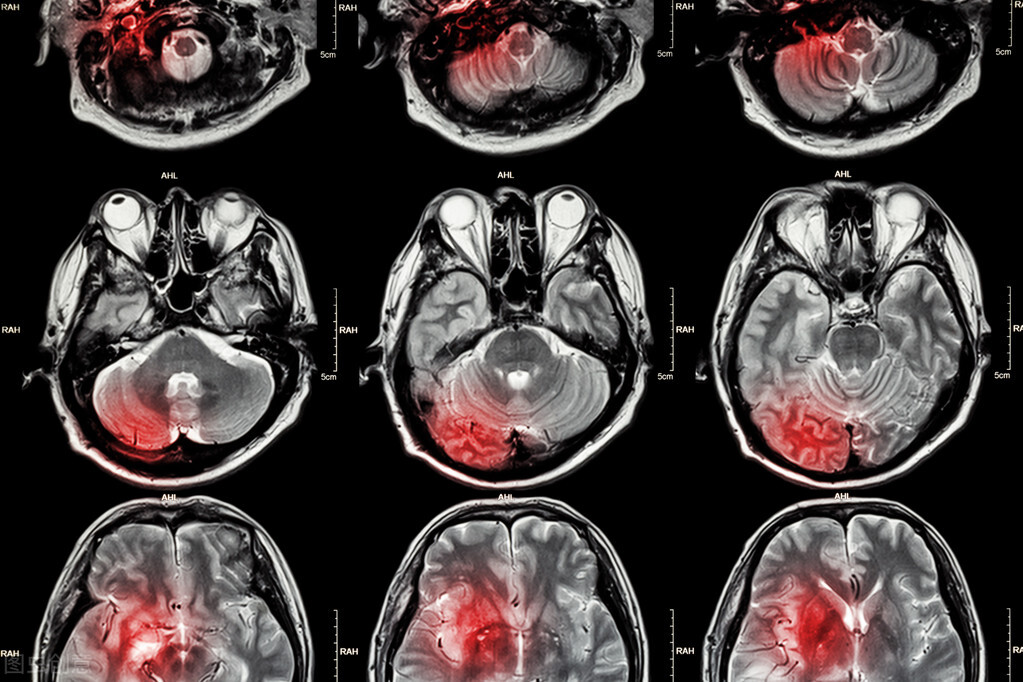

随着颈动脉狭窄程度的加深,脑部的缺氧症状也会更加明显。这个时候患者可能会出现 脑部缺氧的症状 ,比如 头晕、肢体麻木、眼前发黑、一过性的失语和瘫痪等,严重的时候患者会出现持续性的脑缺血的症状(具体如上)。